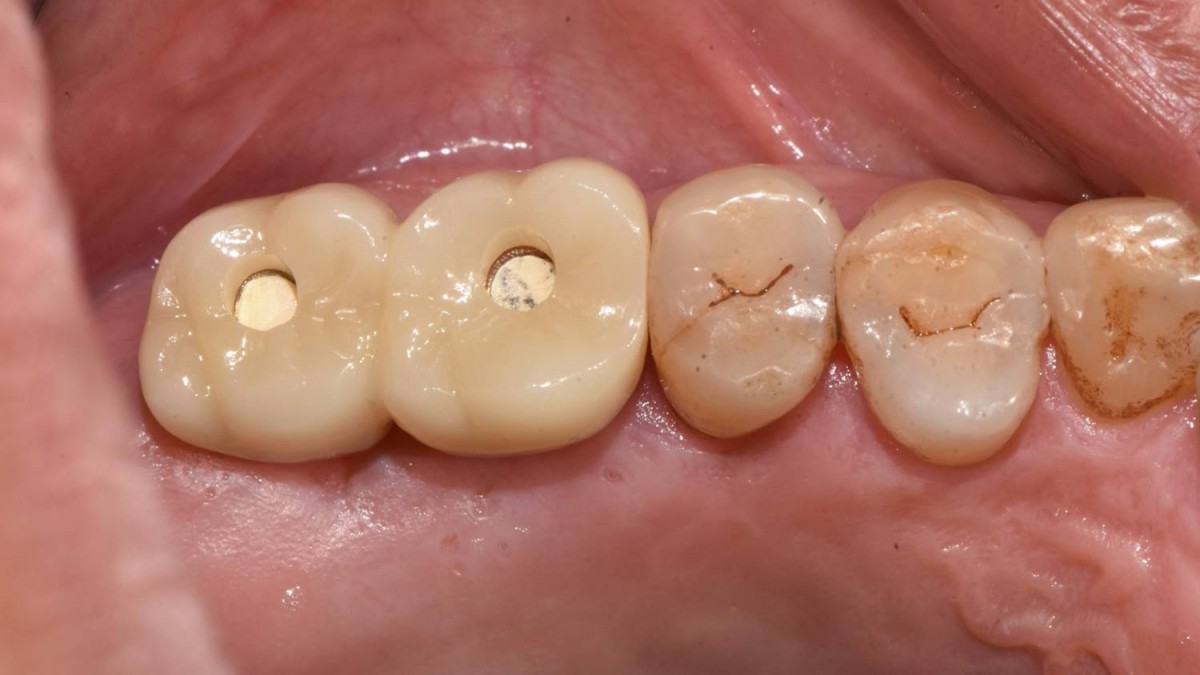

Maxillary Sinus Graft, 2 Implants, Crown Contouring

<GCaks> A 56-year-old male patient had pain-inducing caries, and perio-involved tooth mobility resulted in a tooth fracture at 1st molar. And it was removed months ago. He was a heavy smoker and showed poor oral hygiene.